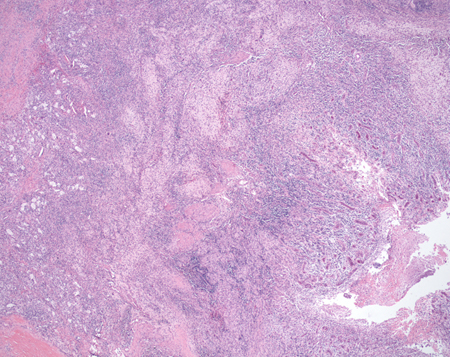

Na pielonefrite xantogranulomatosa, a obstrução e a infecção causam a infiltração de monócitos e o desenvolvimento de macrófagos preenchidos de lipídios, principais características patológicas da doença.[25][Figure caption and citation for the preceding image starts]: Pielonefrite xantogranulomatosa: visualização microscópica de muito baixa potência que mostra infiltrados celulares extensivos e granulomas. Observe a destruição acentuada da arquitetura renal normalCortesia do Dr. Jean L. Olson, MD, Departamento de Patologia, Universidade da Califórnia, San Francisco, EUA [Citation ends].